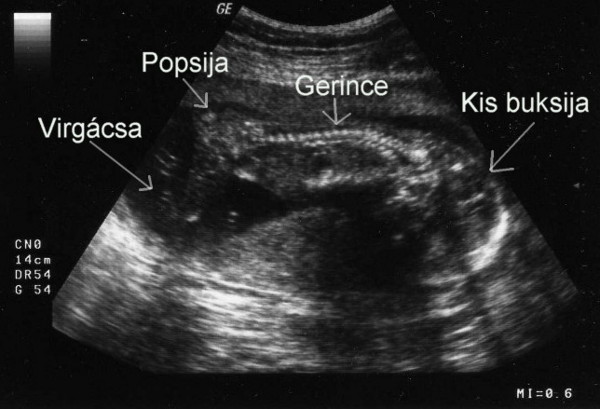

UH: befeküdt a drágánk fejfekvésbe. Ez nem is lett volna gond, ha nem a hátát és a popsiját mutatja egész uh alatt......... A kis arcocskáját befelé fordította, nem is láttuk! A doktornő is megszenvedett vele, pl. a szivecskéjét nem is tudta alaposan megnézni. Mondta neki, hogy forduljon meg, de nem hallgatott rá. Bízunk benne, hogy a jövő hét csütörtöki 4d-re megfordul, mert ha nem, hát nem sok esélyünk lesz bármire is. VAgyis semmi értelme nem lesz az uh-nak. Addig meg kell fordítanunk. Valahogy

Nemét nem akarta az orvos megmondani, mert nem nagyon volt benne biztos. Azt mondja, ha majd biztosabb lesz. Erre én rákérdeztem, hogy kisfiú? Ő visszakérdezett, hogy honnan gondolom? Mondtam, hogy megérzés. Erre ő: ő is úgy érzi. Nehéz volt megállapítani, hogy fiúcska, mert a lába közt sok volt a köldökzsinór. Megnézte áramlásmérővel, ahol volt áramlás, az a köldökzsinór volt, ahol meg nem, a kis kukija.